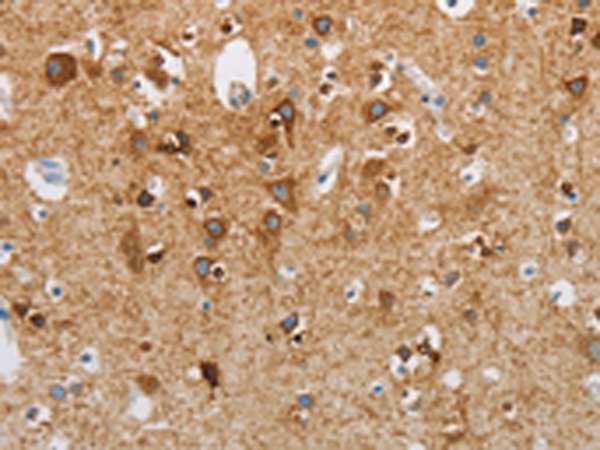

IHC positive control: |

Human brain and Human liver cancer |

IHC Recommend dilution: |

25-100 |